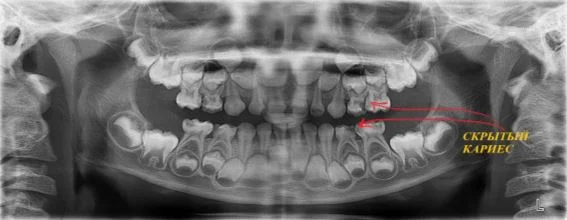

- вероятное наличие невидимых при обычном осмотре кариозных полостей;

Панорамный снимок - это не то, на чем можно сэкономить. Малейшая ошибка в диагностике при отсутствии снимка - это риск серьезных упущений в лечении и дополнительных затрат.